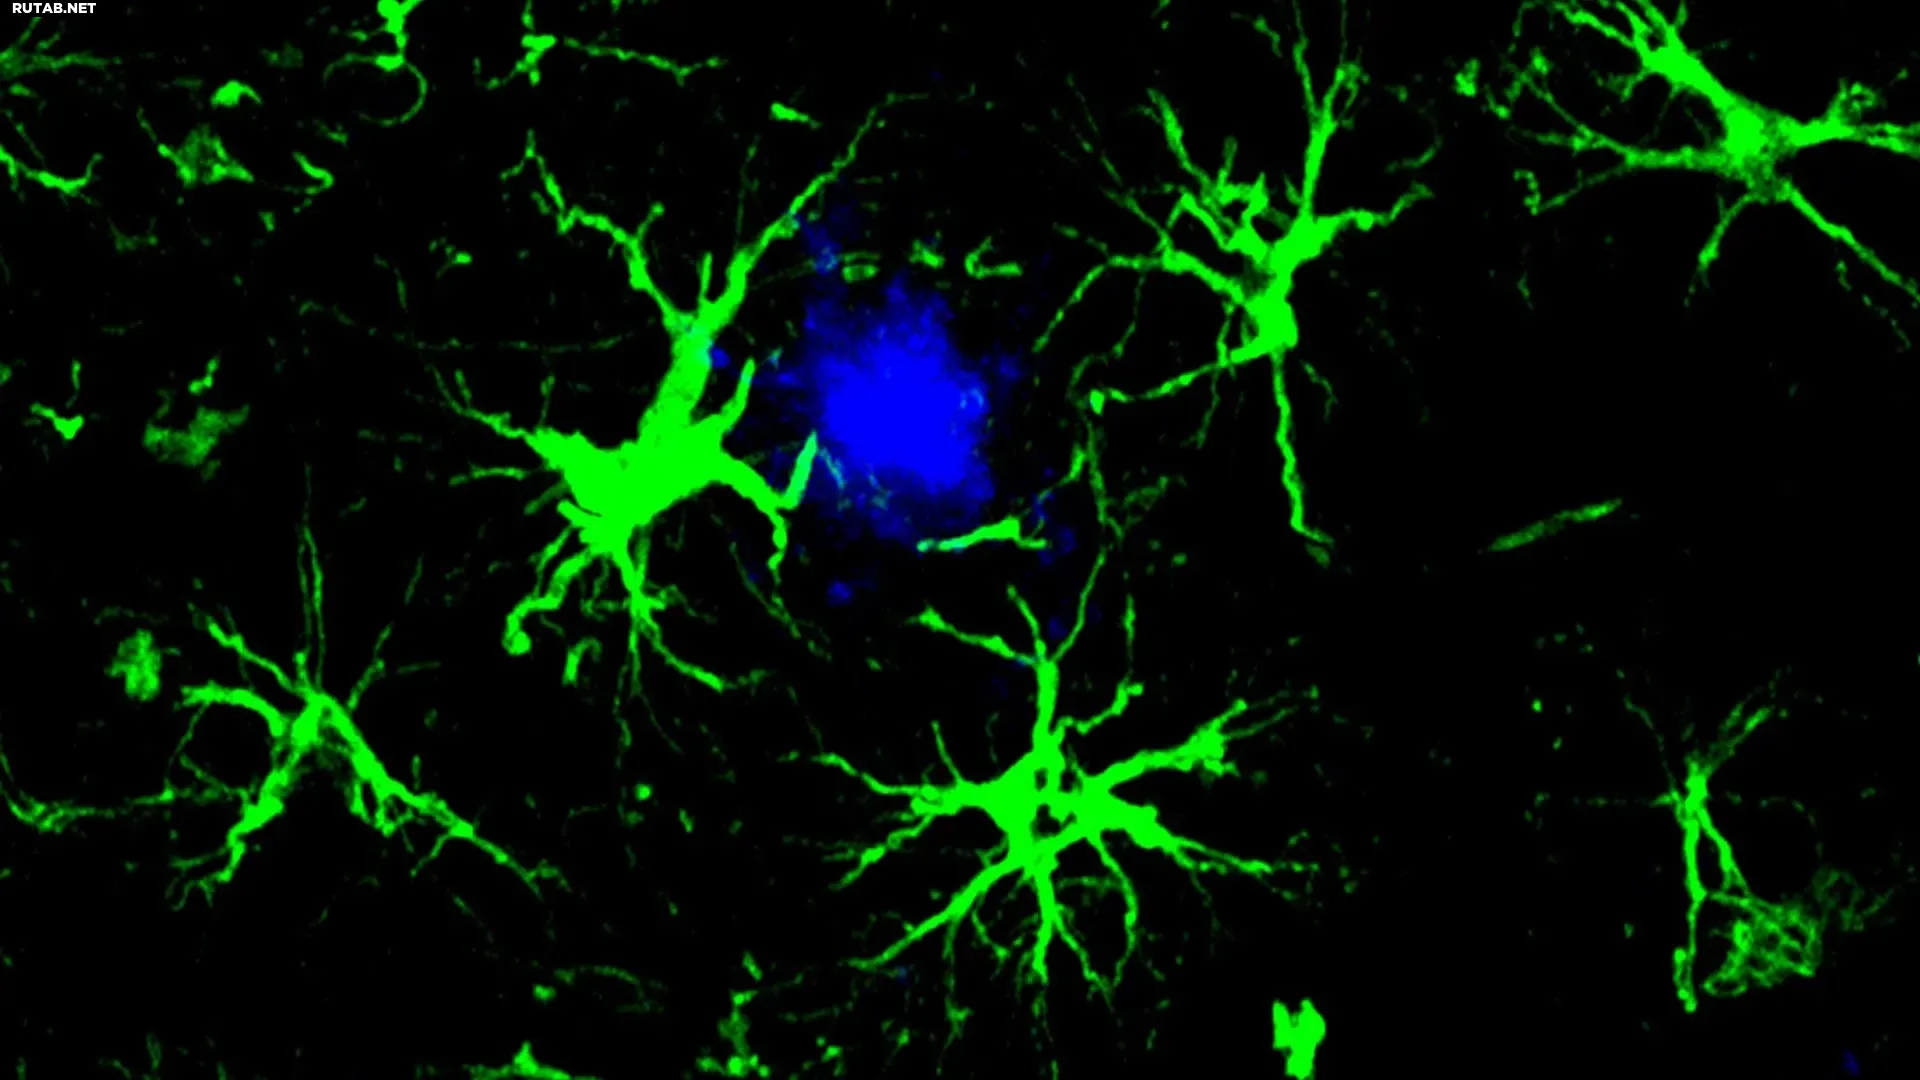

Исследователи из Медицинской школы Вашингтонского университета в Сент-Луисе разработали экспериментальную клеточную иммунотерапию, которая превращает астроциты — вспомогательные клетки мозга — в «суперуборщиков», способных удалять вредные амилоидные бляшки, связанные с болезнью Альцгеймера.

Новый подход вдохновлен CAR-T-терапией, применяемой в онкологии. Ученые генетически модифицировали астроциты, снабдив их химерным антигенным рецептором (CAR), который позволяет клеткам находить и поглощать белки бета-амилоида.

В экспериментах на мышах, генетически предрасположенных к болезни Альцгеймера, однократная инъекция модифицированных CAR-астроцитов показала впечатляющие результаты. У молодых мышей, получивших терапию до появления бляшек, их образование было полностью предотвращено. У более старых мышей с уже накопленными отложениями количество амилоидных бляшек в мозге сократилось примерно наполовину.